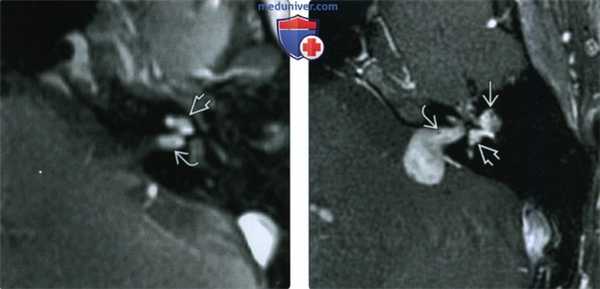

(Слева) При аксиальной МРТ Т1ВИ определяется минимальный гиперинтенсивный сигнал в преддверии и улитке у пациента с вестибулокохлеарной шванномой.

(Справа) При аксиальной MPT Т2ВИ визуализируется материал с сигналом, соответствующим мягким тканям, замещающий сигнал, типичный для нормальной жидкости в преддверии и улитке у пациента с ИЛШ вестибулокохлеарного типа. Эти опухоли чаще распознаются на МРТ высокого разрешения (Т2) в условиях высокой настороженности.

(Слева) При аксиальной МРТ Т2 ВИ определяется ИЛШ трансмакулярного типа в виде материала с интенсивностью сигнала, соответствующей мягким тканям, заполняющего преддверие и распространяющегося вдоль ветвей преддверного нерва до дна дистальных отделов внутреннего слухового канала (ВСК).

(Справа) При аксиальной МРТ Т1ВИ у этого же пациента определяется контрастное усиление интравестибулярной и дистальной интраканаликулярной части этой трансмакулярной шванномы. Минимальное отличие параметров контрастного усиления обусловлено эффектом усреднения объема.